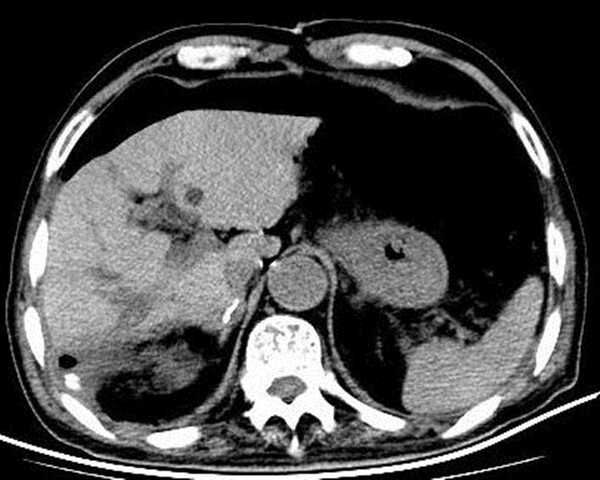

手术后